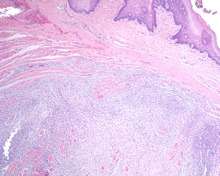

Alcian blue (pH at 2.5) stains the myxoid background material brightly blue in this ectomesenchymal chondromyxoid tumor of the tongue. - Mucicarmine will also highlight the stromal matrix (pink).